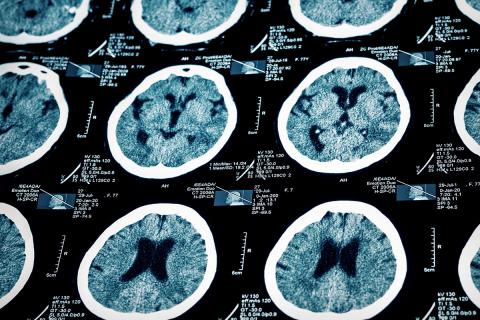

Draper’s latest biomedical breakthrough is a technique that can predict an Alzheimer’s patients cognitive state three years into the future in such areas as learning, memory and language comprehension. (Credit: Shutterstock)